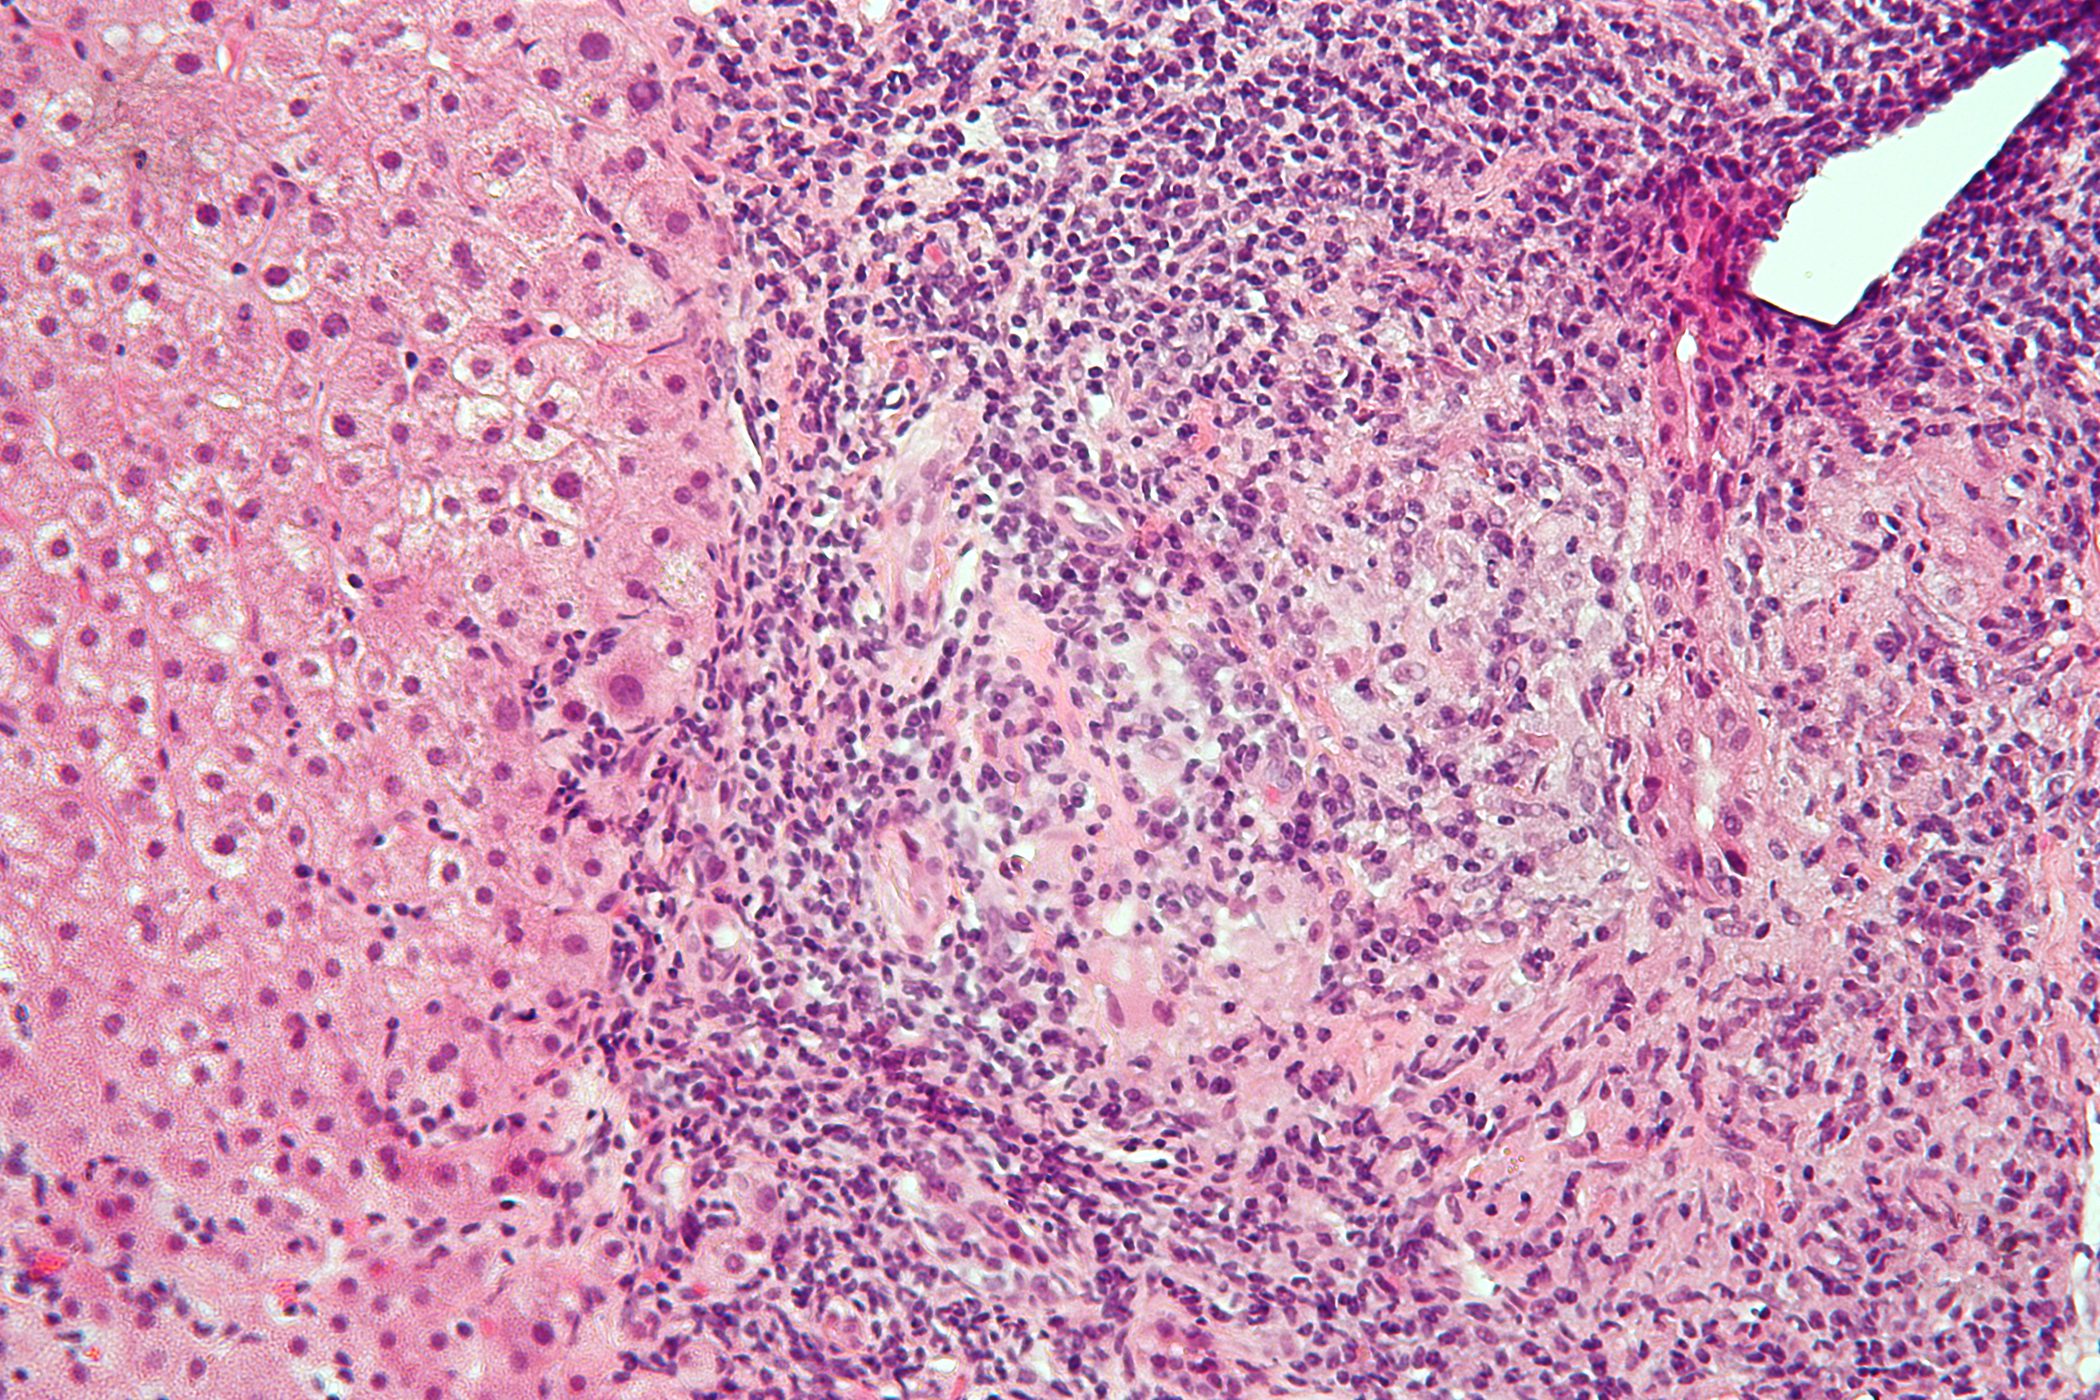

Bittere Bilder: Gallenblasenerkrankungen

«BitterSüss» lautete das Motto der 20. Fortbildungstagung des KHM 2018. In einem Hauptreferat präsentierten Prof. Dr. med. Stephan Vavricka und Dr. med. Regula Capaul fünf Pathologien der Gallenblase anhand realer...…